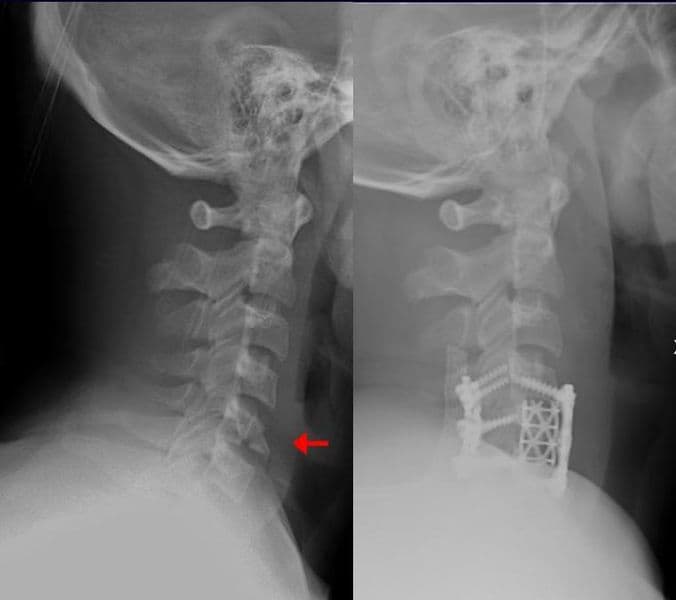

Alexandre Terrier, Frédéric Vauclair, Patrick Goetti